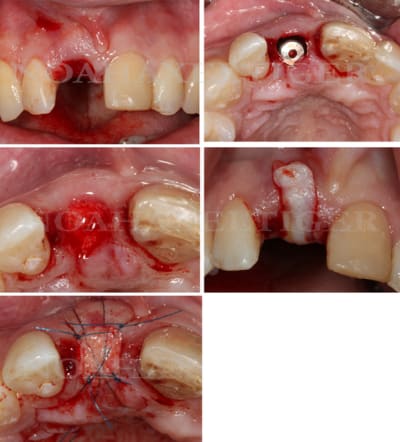

Tout à fait d'accord growler et c'est d'ailleurs ce que l'on peut voir sur le cas suivant. Fracture radiculaire, aucune infection periradicualire. Extraction et implantation immediate. Espace existant entre l'implant et l'alvéole est comblé par du BioOss. Un logement sous gingival est formé en vestibulaire et palatin de facon à pouvoir recouvrir le tout par BioGide et un conjonctif enfoui.

L'implant est de 15mm mais l'alvéole était large et 50% environ de la surface implantaire n'était en contact qu'avec du BioOss. J'ai pour cela préféré enfouir.